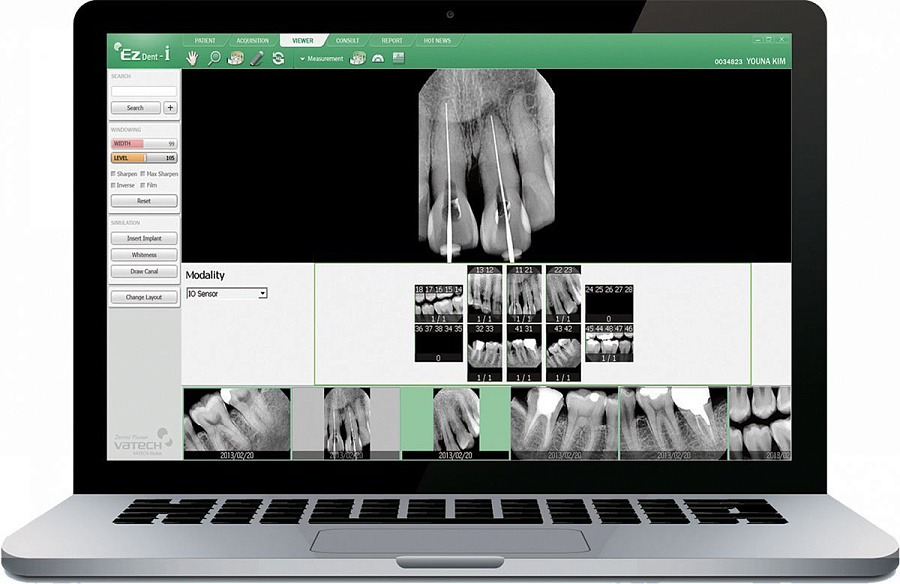

Радиовизиограф EzSensor - Ваш партнер в цифровой диагностике

- Гибкость в выборе 1 из 3 размеров датчика под задачу диагностики

- Высококачественные снимки

- Быстрый и эффективный рабочий процесс

Программное обеспечение для обработки 3D исследований Ez3D-i